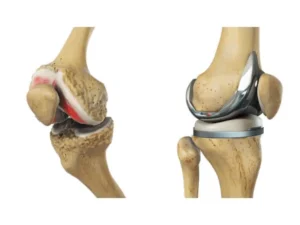

جراحی پای پرانتزی چگونه انجام میشود؟ تجربه بیماران

جراحی پای پرانتزی روشی است که برای برطرف کردن انحراف استخوان ساق و اصلاح زاویه زانو انجام میشود. افرادی که با این مشکل روبهرو هستند، اغلب درد، محدودیت در راه